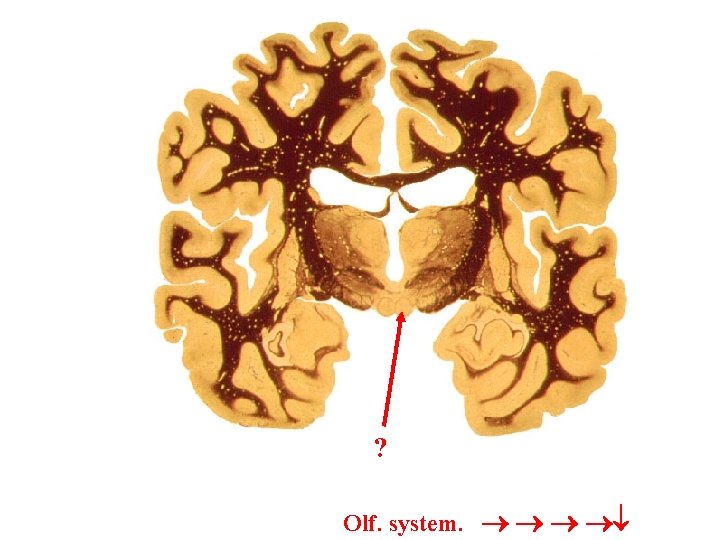

Olf system LIMBIC SYS Limbic System Limbic lobe

? Olf. system.

Limbic System: Limbic lobe + hippo. , fornix, MMBs, MTT, ant. nuc. thal. , cingulate cortex, cingulum, parahippo. gyrus then into hippo. stria terminalis? Papez circuit? Limbic Lobe